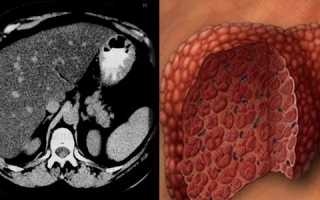

На фото печень при жировом гепатозе 3 степени в разрезежировом гепатозе 3 степени в разрезе на макропрепарате и при КТ исследовании пациента: